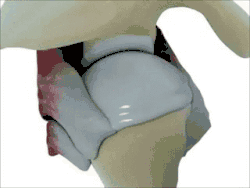

The shoulder joint (or glenohumeral joint from Greek glene, eyeball, + -oid, 'form of', + Latin humerus, shoulder) is structurally classified as a synovial ball-and-socket joint and functionally as a diarthrosis and multiaxial joint. It involves an articulation between the glenoid fossa of the scapula (shoulder blade) and the head of the humerus (upper arm bone). Due to the very loose joint capsule, it gives a limited interface of the humerus and scapula and is the most mobile joint of the human body.

Structure

The shoulder joint is a ball-and-socket joint between the scapula and the humerus. The socket of the glenoid fossa of the scapula is itself quite shallow, but it is made deeper by the addition of the glenoid labrum. The glenoid labrum is a ring of cartilaginous fibre attached to the circumference of the cavity. This ring is continuous with the tendon of the biceps brachii above.